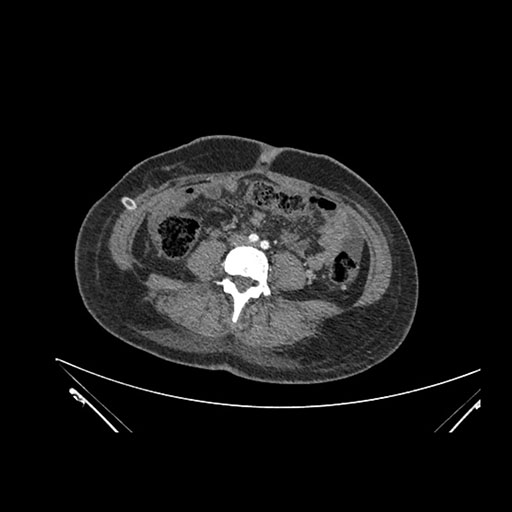

Axial Venous